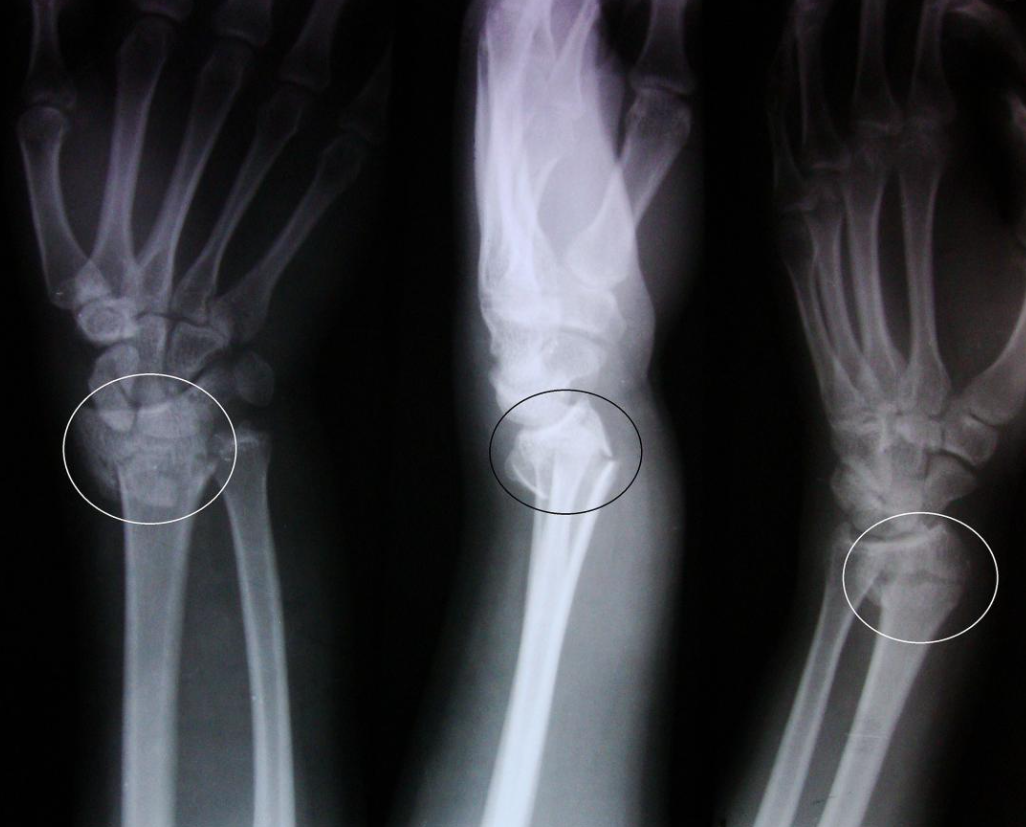

Colles Fracture: Causes, Treatment, and Recovery A...